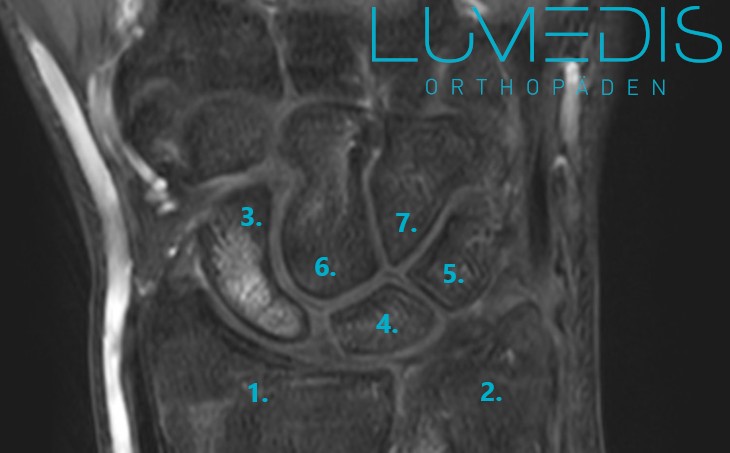

MRT eines Handgelenk mit Handwurzel mit Bandverletzung

Abbildung des TFCC am Handgelenk mit allen Bändern